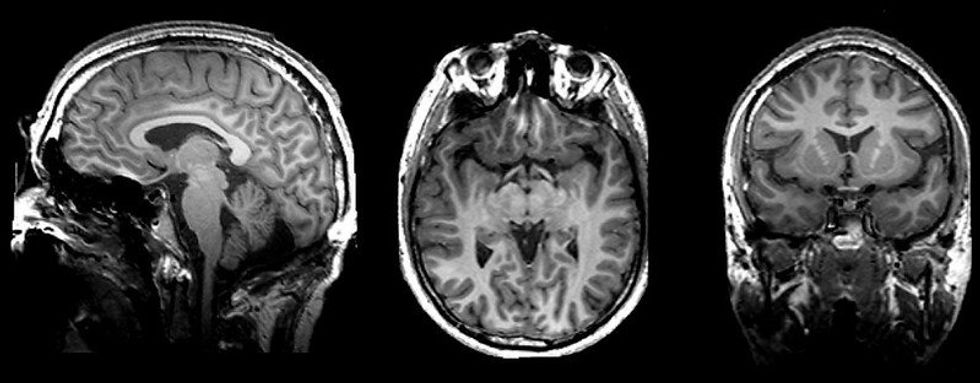

The team, led by behavioral neuroscientist Daphna Joel, analyzed the MRI scans of 1,400 individuals, mapping things like gray matter (gooey stuff that handles sensation, emotion ... pretty much everything), white matter (the gooey stuff that carries messages between areas of gray matter), and a host of personality traits along the way.

That it's pretty dang rare for a given brain to demonstrate only male or female characteristics.

The plain truth is that our brains flat out can't be separated into two distinct gender categories.

Our brains, the researchers say, are more like "mosaics" — wonderful mixtures of the traits we usually associate with men or women.

That's not to say the study found no differences between the brains of men and women, but rather that a brain consisting of almost all male or female features was pretty uncommon, and that it'd be really tough to tell if a person were biologically male or female just by looking at their brain.

Yes, on average there are certain differences in brain size, connections between hemispheres, size of the hippocampus or amygdala.

But this particular study found you couldn't make any concrete predictions about how a person's brain would look or function just based on their biological sex.

"Although there are group-level differences between men and women in brain structure, most brains are composed of unique mosaics of brain features, some in a form more common in women compared to men, and some in a form more common in men compared to women," she wrote.

"Moreover, the brain architectures typical of women are also typical of men, and vice versa... Sex category provides little information on an individual’s specific brain architecture or on how their brain is similar or different from someone else’s."